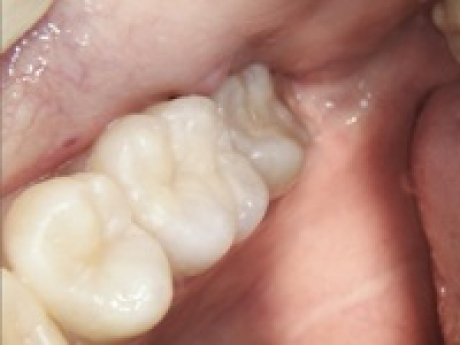

case4